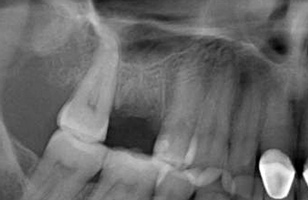

Due to the need for medical treatment for shoulder and neck issues, the patient was delayed in returning to the office for subsequent evaluation. At the 7-month postoperative appointment, the socket was assessed and a panoramic radiograph was taken to evaluate the bone at the planned implant site (Figure 1). The socket was filled with bone that was indistinguishable from the patient's native bone adjacent to the site. Insufficient height to place an implant was noted, which would require a crestal sinus lift prior to implant placement. A cone-beam computed tomography (CBCT) scan was ordered for planning purposes. Planning software was used to properly position a 5.2 x 10 mm implant for placement into the edentulous site, confirming that some elevation of the sinus would be required (Figure 2 and Figure 3). This data was used to order a surgical stent to guide implant placement (Figure 4).

(1.) Radiograph of the missing maxillary molar and available bone between the crest and maxillary sinus.

Figure 1